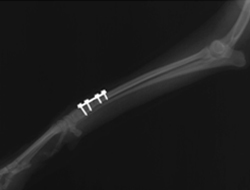

骨折

骨折手術にはプレート固定法、創外固定法、ピンニング法、インターロッキング法と各器具があり、骨折の状態により、手術法を検討し実施しています。

当院での骨折の手術症例

創外固定